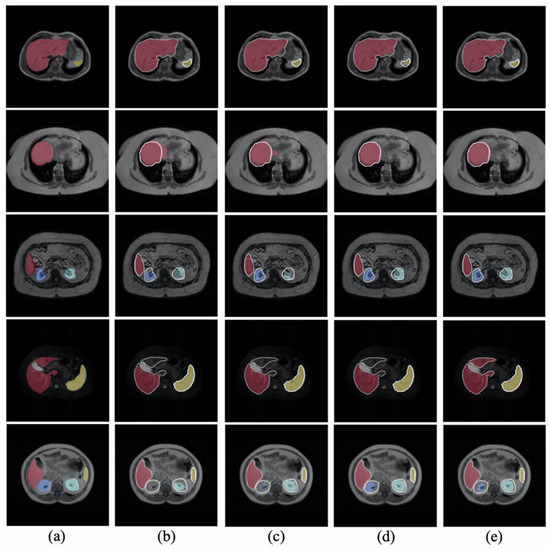

- We developed the contour-aware CNN and employed the voting strategy in our joint optimization framework.

- We validated our framework using two public datasets, abdomen MRI (CHAOS Challenge) and hippocampus MRI (the Medical Segmentation Decathlon), and could achieve comparable performance compared with other related methods.